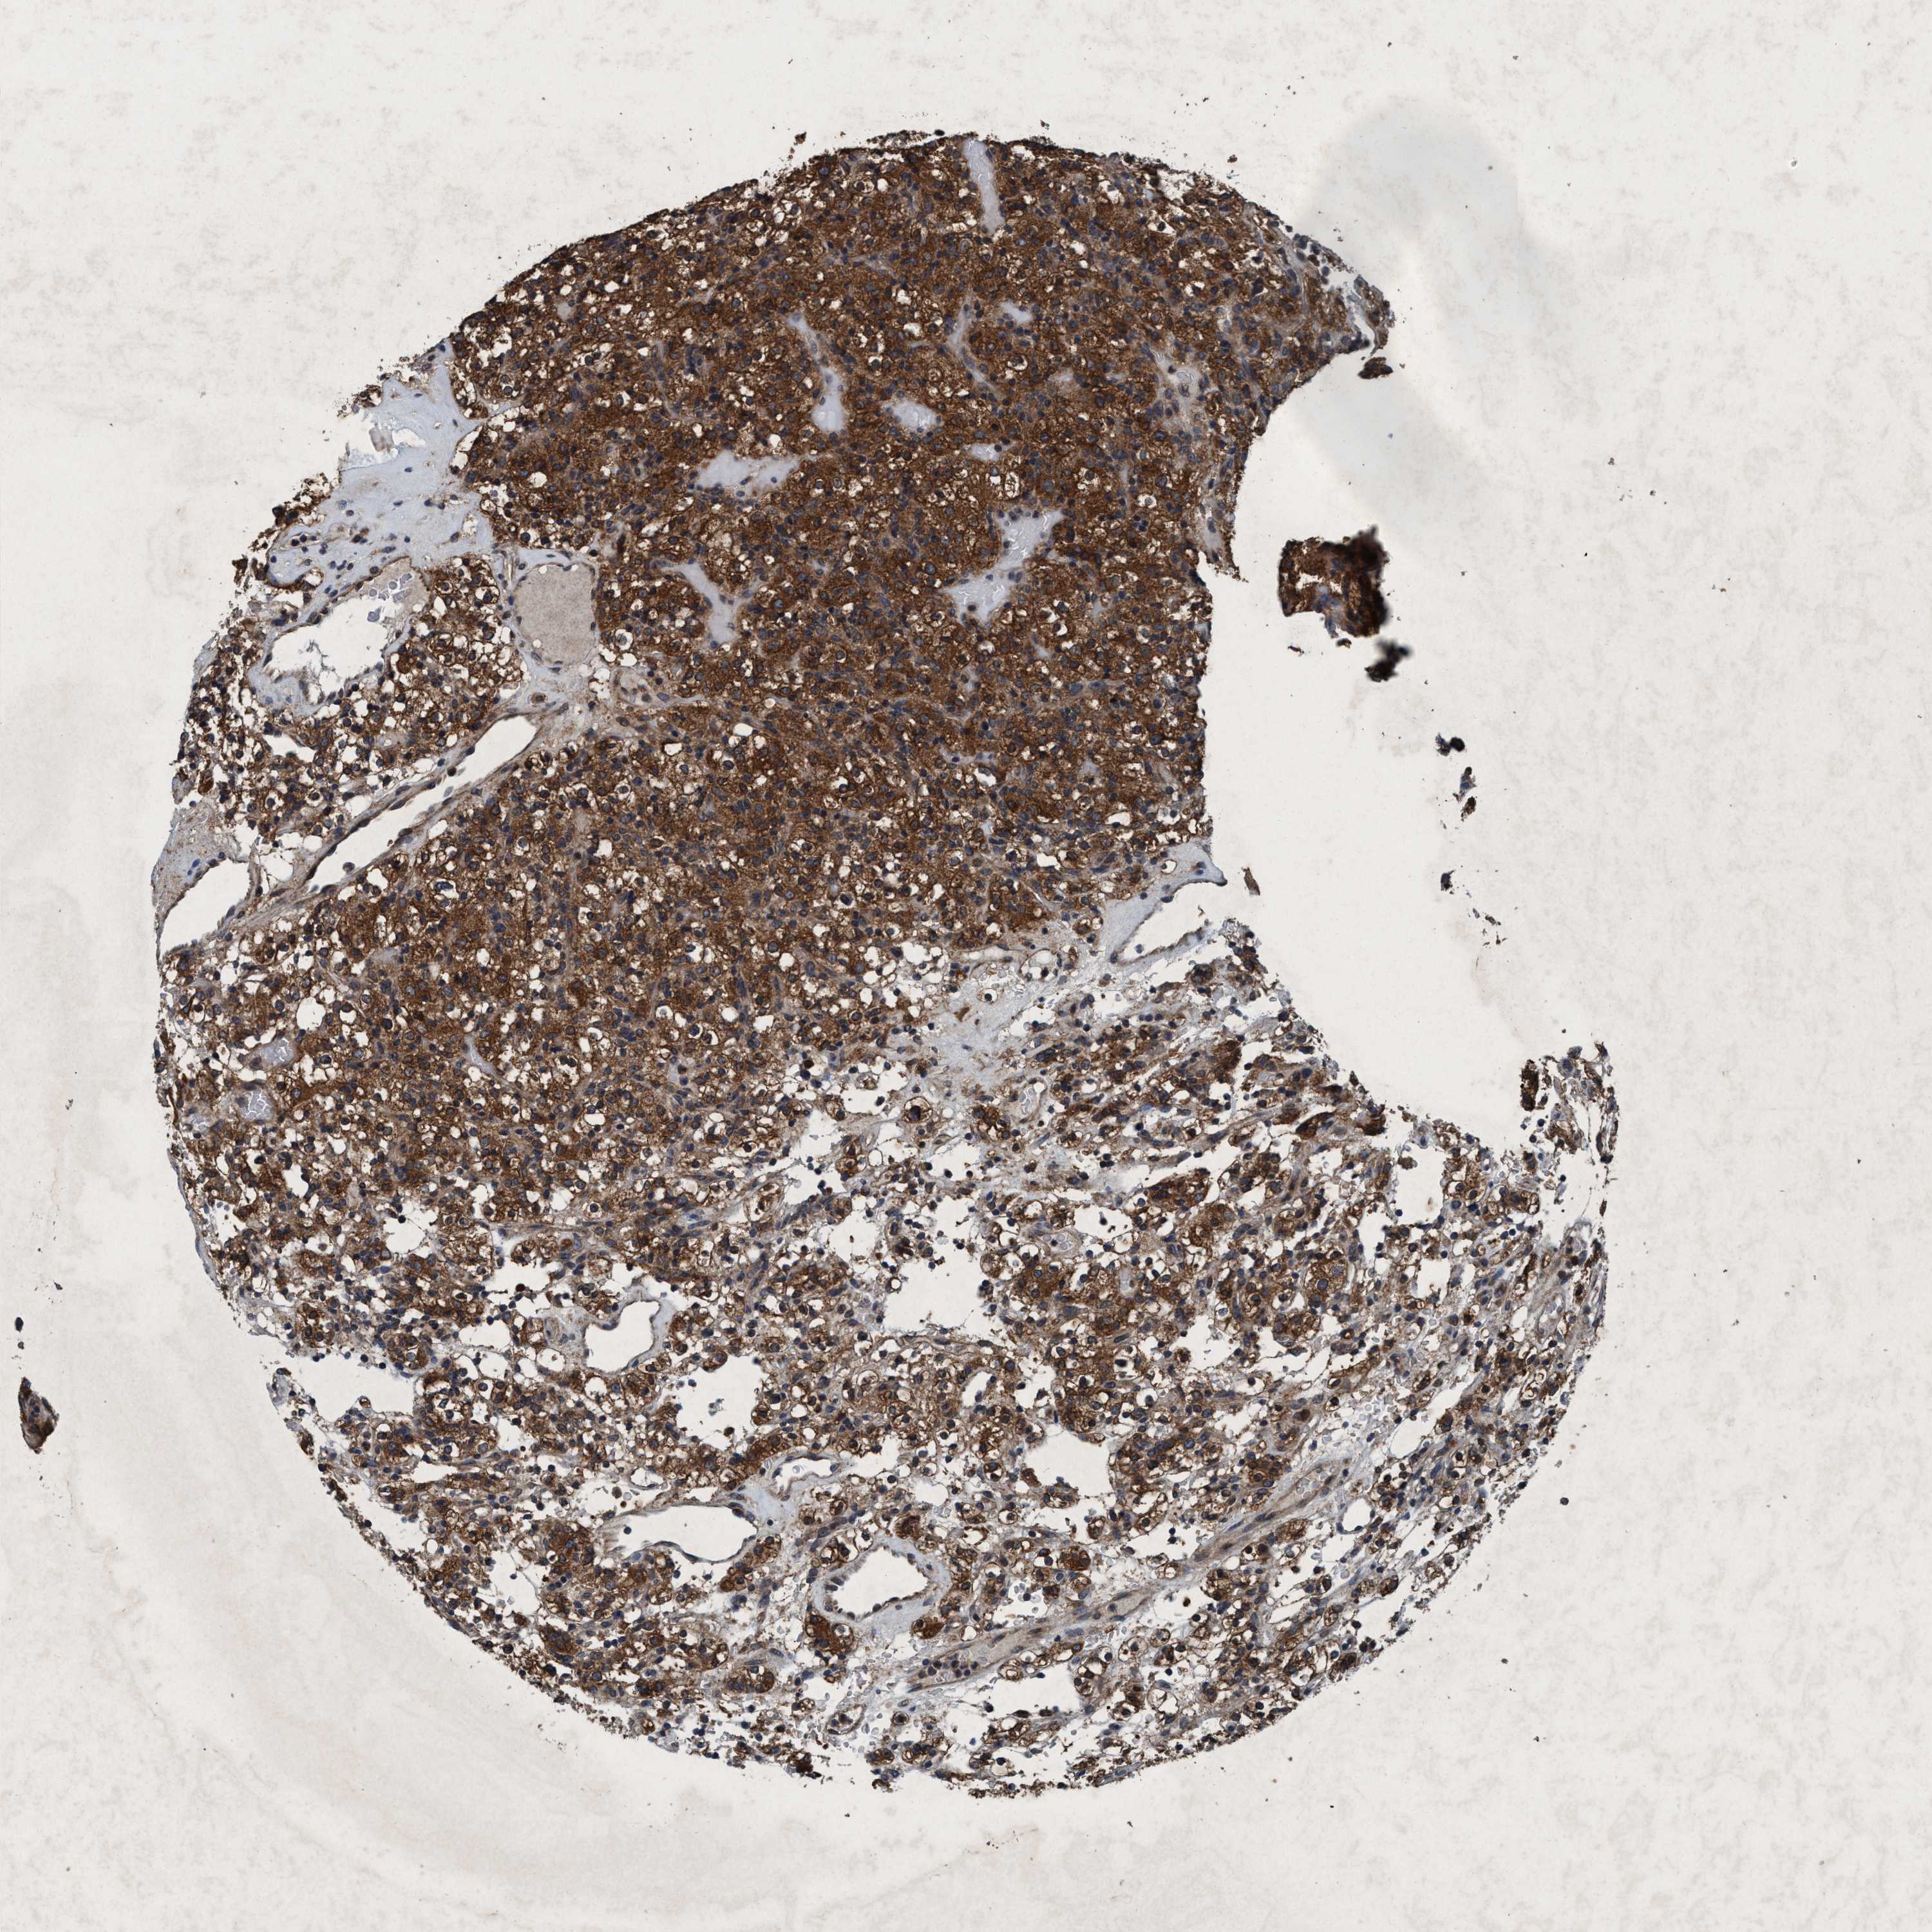

CANCER RENAL CANCER Show tissue menu

Renal cancer

Human cancer

Kidney chromophobe

Kidney renal clear cell carcinoma

KIDNEY CHROMOPHOBE (TCGA) - Interactive survival scatter ploti

The Survival Scatter plot shows the clinical status (i.e. dead or alive) for all individuals in the patient cohort, based on the same data that underlies the corresponding Kaplan-Meier plots. Patients that are alive at last time for follow-up are shown in blue and patients who have died during the study are shown in red.

The x-axis shows the expression levels (FPKM) of the investigated gene in the tumor tissue at the time of diagnosis. The y-axis shows the follow-up time after diagnosis (years). Both axes are complimented with kernel density curves demonstrating the data density over the axes. The top density plot shows the expression levels (FPKM) distribution among dead (red) and alive patients (blue). The right density plot shows the data density of the survived years of dead patients with high and low expression levels respectively, stratified using the cutoff indicated by the vertical dashed line through the Survival Scatter plot. This cutoff is automatically defined based on the FPKM cutoff that minimizes the p-score. The cutoff can be changed by dragging the vertical line or by entering a cutoff value in the square labeled "Current cut-off".

Under the Survival Scatter plot the p-score landscape (black curve; left axis) is shown together with dead median separation (red curve; right axis). Dead median separation is the difference in median mRNA expression between patients who have died with high and low expression, respectively. It is calculated as follows: median FPKM expression of dead patients with high expression - median FPKM expression of dead patients with low expression. This is intended to aid the user in visually exploring custom cutoffs and the associated p-scores and dead median separation.

Individual patient data is displayed and can be filtered by clicking on one or more of the category buttons on the top of the page. Categories describing expression level and patient information include: high, low, alive, dead, female, male and tumor stages. The scale of the x-axis can be toggled between linear and log-scale by clicking on the "x log" button. Mouse-over function shows TCGA ID, patient information and mRNA expression (FPKM) for each patient.

& Survival analysisi

Kaplan-Meier plots summarize results from analysis of correlation between mRNA expression level and patient survival. Patients were divided based on level of expression into one of the two groups "low" (under cut off) or "high" (over cut off). X-axis shows time for survival (years) and y-axis shows the probability of survival, where 1.0 corresponds to 100 percent.

AKT1S1 is not prognostic in Kidney Chromophobe (TCGA)

Best expression cut offi

Based on the FPKM value of each gene, patients were classified into two groups and association between prognosis (survival) and gene expression (FPKM) was examined. The best expression cut-off refers the FPKM value that yields maximal difference with regard to survival between the two groups at the lowest log-rank P-value. Best expression cut-off was selected based on survival analysis .

When clicking on this number, the vertical dashed line indicating cut-off, the interactive survival plot, and the Kaplan-Meier curve will be adjusted to show results based on the best expression cut-off.

: 25.24

P scorei

Log-rank P value for Kaplan-Meier plot showing results from analysis of correlation between mRNA expression level and patient survival.

N/A

TCGA RNA samplesi

RNA-seq data is reported as average FPKM (number Fragments Per Kilobase of exon per Million reads), generated by the The Cancer Genome Atlas (TCGA) .

Normal distribution across the dataset is visualized with box plots, shown as median and 25th and 75th percentiles. Points are displayed as outliers if they are above or below 1.5 times the interquartile range. FPKM values of the individual samples are presented next to the box plot.

Average pTPM 35.1

Number of samples 64